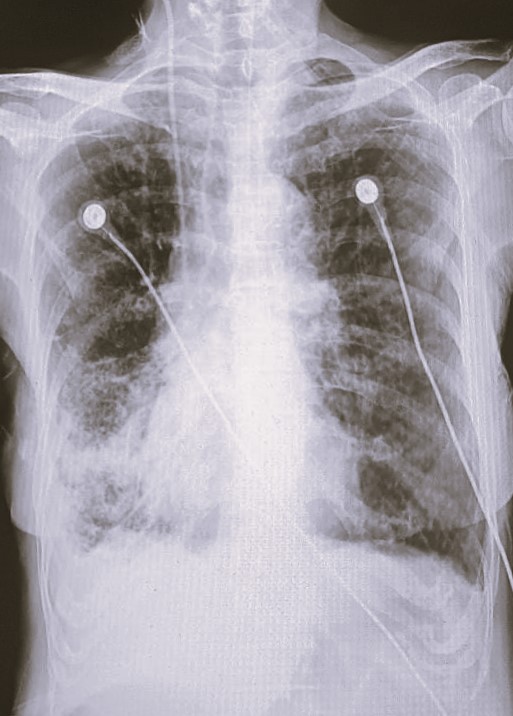

| 102 | IGGMC, Nagpur, Nagpur | P2 | 29-4370 | Prachi Bawane | Consent taken on Paper | 17 Yrs. |

Provisional Diag : PTB?

Final Diag : Active Pulmonary Tuberculosis With Tuberculi? Right Sided Pleural Effusion |

TB Case (Confirmed) | Bilateral ill Defined, No Homogenous Reticulonodular opacities, Right CP Angle Blunting | Abnormality visible on x-ray |